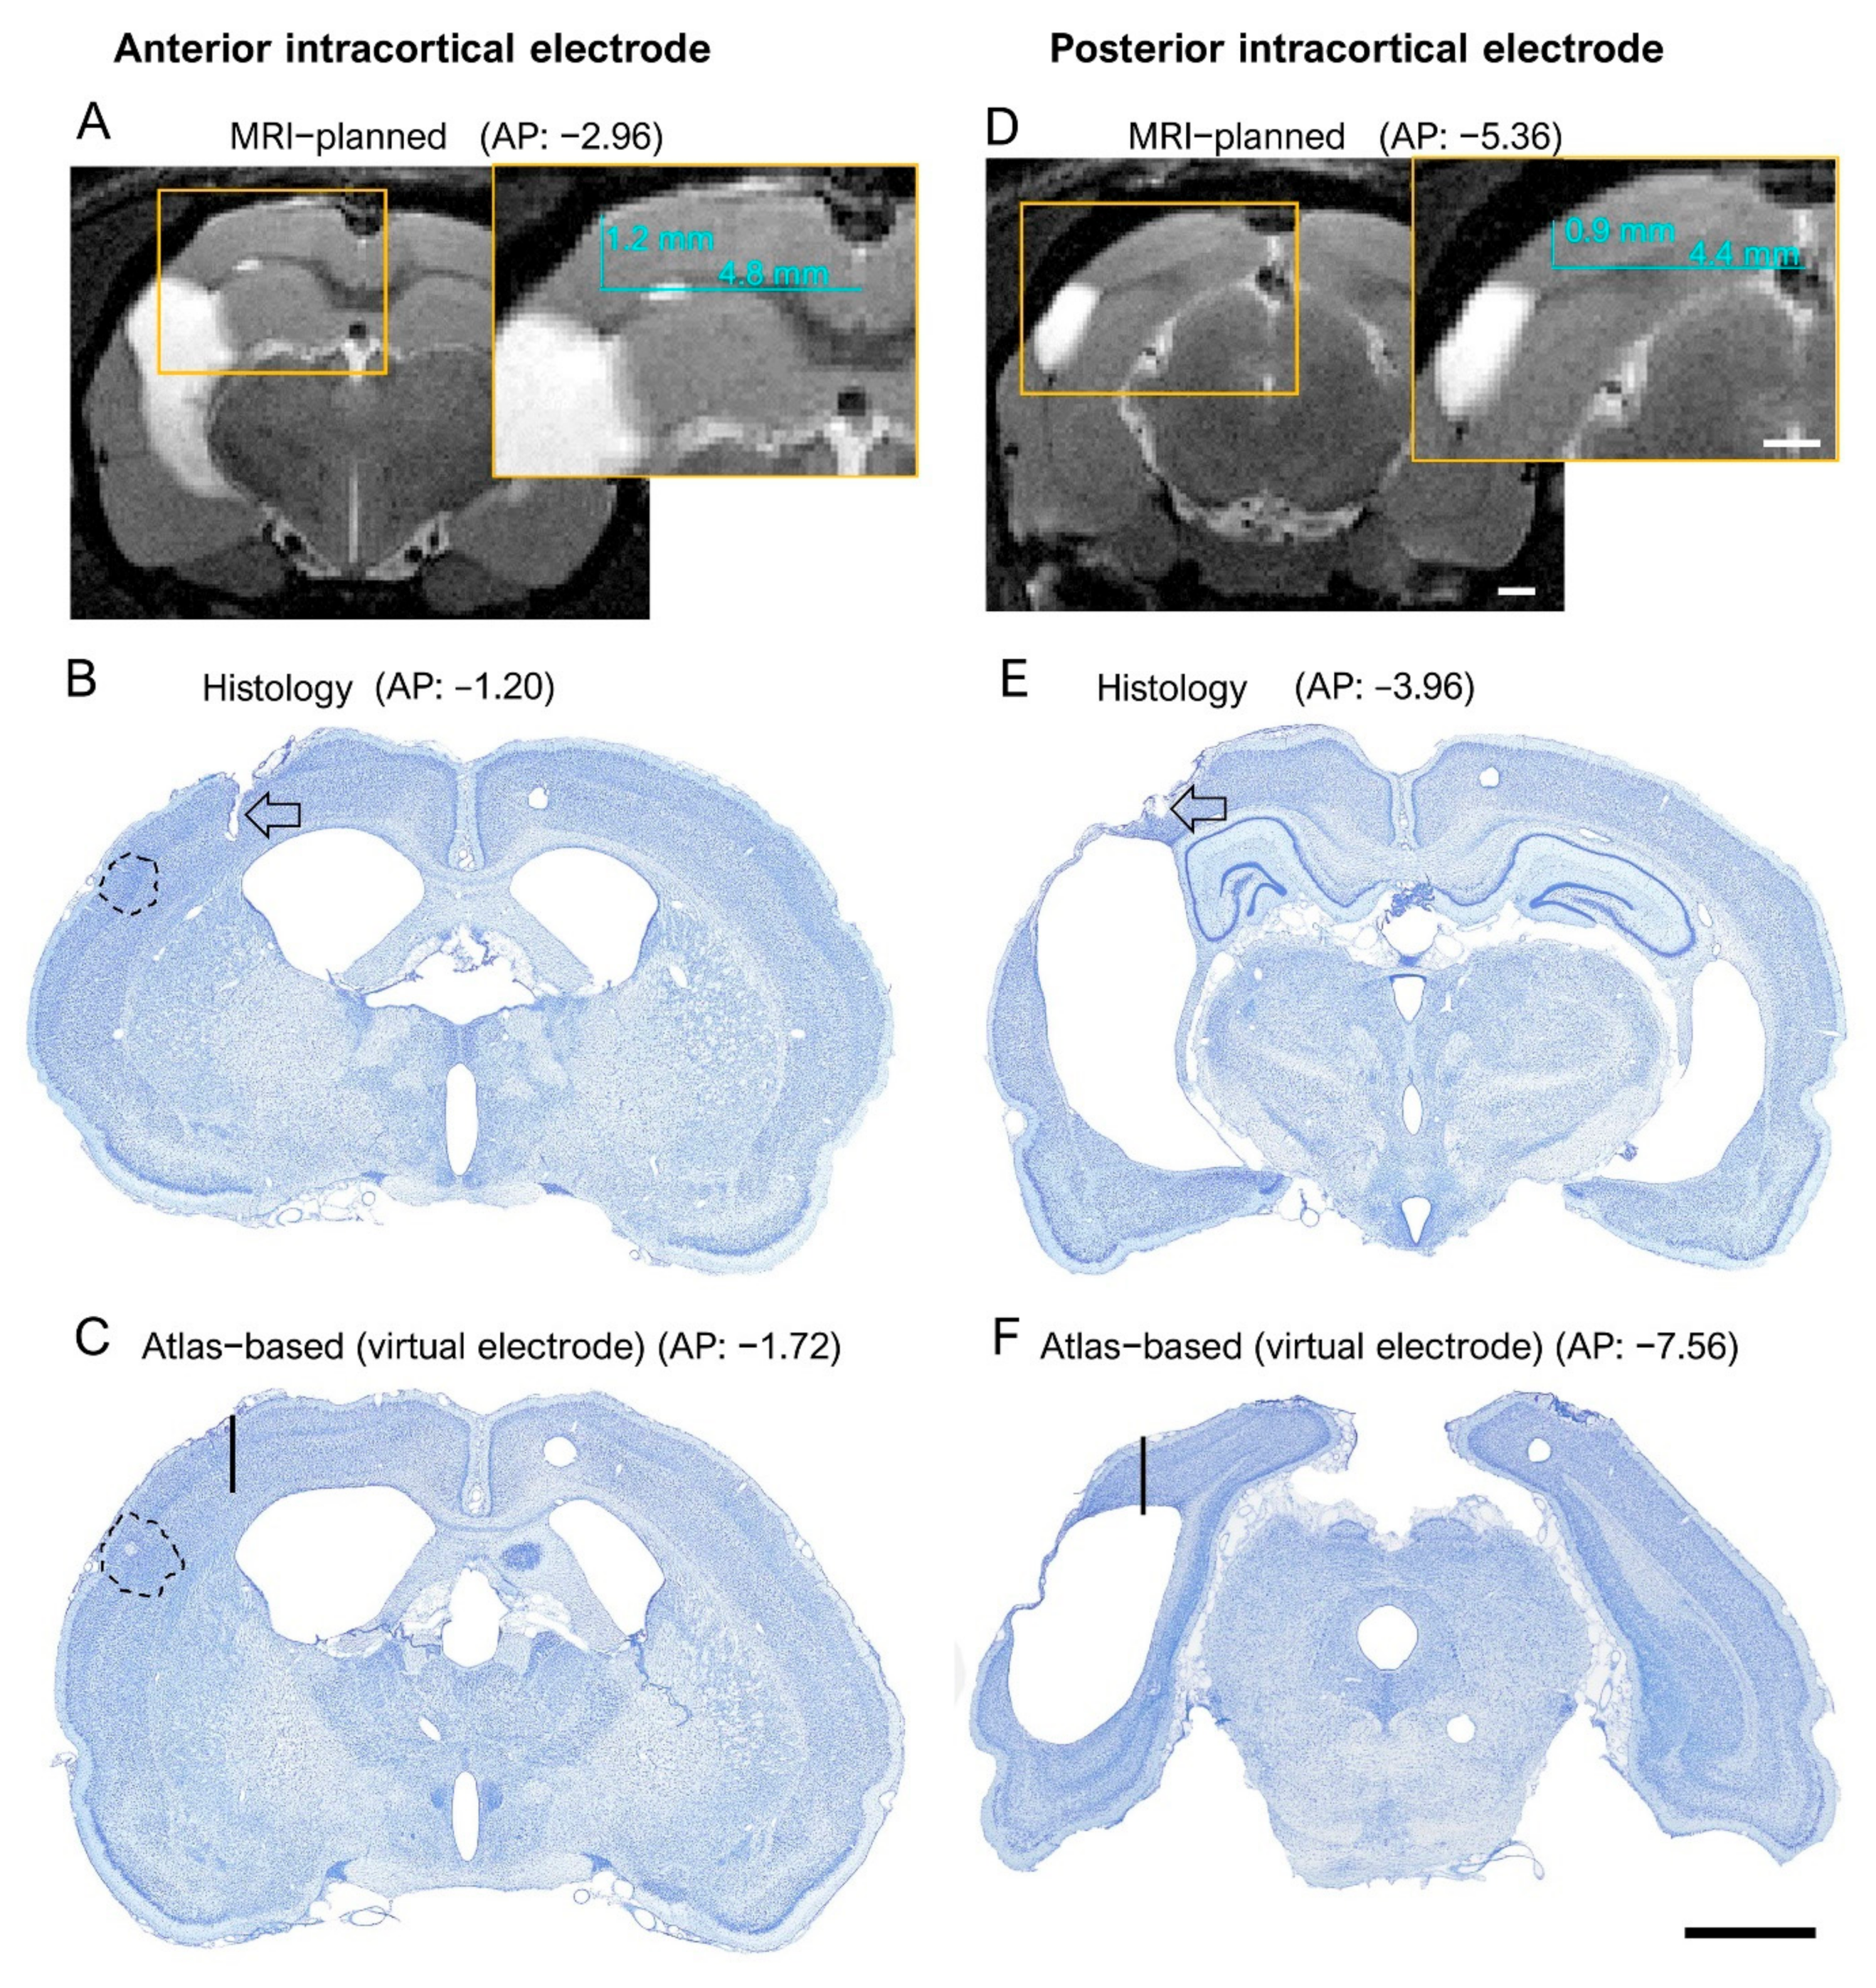

Figure 6.

Histological confirmation of the success of MRI-guided electrode placement. Left panel (A–C): Anterior intracortical electrode MRI-planned coordinate, histological confirmation, and “virtual” electrode. Right panel: Posterior intracortical electrode MRI-panned coordinate histological confirmation, and “virtual” electrode. (A) T2-weighted MRI and (B) histological images showing the MRI-guided (insert) and histology-confirmed “true” location of the anterior intracortical electrode in rat 1139. The anteroposterior (AP) coordinate was estimated by aligning the magnetic resonance images with the rat brain atlas [25]. The mediolateral (ML) and dorsoventral (DV) coordinates (inserts in (A,D)) were determined using ImageJ software (version 1.47v, Wayne Rasband and contributors, National Institute of Health, USA). Note that in this case, the confirmed AP location was about 1.8 mm more rostral than the planned location (−1.20 mm vs. −2.96). Lesion area is denoted in black-dashed-line circle. (C) A “virtual” location of the electrode tip (black line) if the electrode had been implanted to the targeted atlas-based coordinate (−1.75 mm from bregma, 4 mm from midline, 1.8 mm from the surface of the brain). (D) MRI-guided (insert) AP, ML and DV coordinates and (E) histology-confirmed “true” location of the posterior intracortical electrode tip in rat 1139. The black-dashed-line circle denotes the lesion area. Note that the confirmed AP location was approximately 1.4 mm more rostral than the planned location (−3.96 vs. −5.36). Thus, even though both the anterior and posterior intracortical electrodes were more rostral than planned, their tips were recording EEG signals in the perilesional cortex. (F) A “virtual” electrode (black line) at the atlas-based coordinates would have ended up in the lesion cavity. Scale bar in (A,D) = 1 mm, and in (B,C,E,F) = 2 mm.